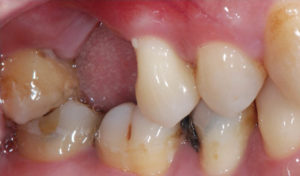

牙周手術案例之三 自強牙醫部落格